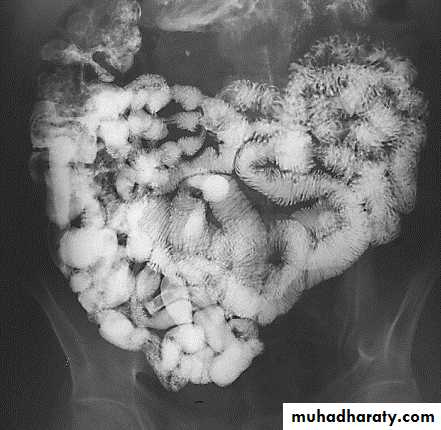

Barium follow-through

• Its contrast examination of the small bowel.

• The indications are:

1. inflammatory bowel disease (crhon's)2. suspected stricture

3. malabsorption

4. enterocutaneous fistula

5. malrotation

6. post-small bowel resection

• The patient drinks a quantity of barium or Gastrografin and images are acquired until the contrast material either reaches an obstruction or enters the large bowel.

Normal appearance of the small bowel

• The normal SB occupies the central & lower abdomen.• The terminal ileum enters the medial aspect of the cecum through the ileocecal valve.

• Normal mucosa exhibit a feathery appearance [Valvulae conniventes].

• The diameter of SB loop should not exceeds 3 cm .

• Jejunum is wider than the ileum.

• Valvulae conniventes is conspicuous at jejunum more than the ileum.